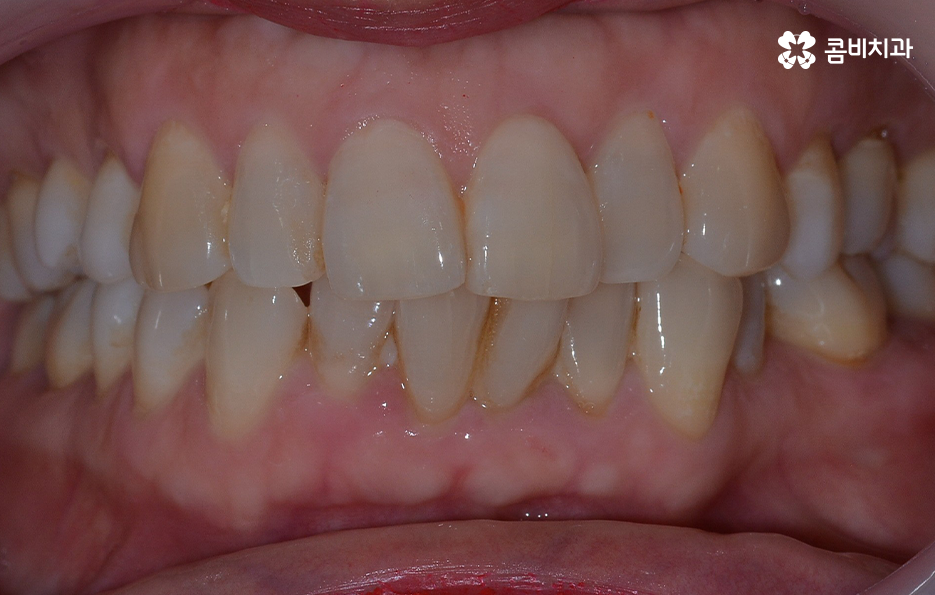

오늘 보시는 교정 사례의 경우를 보시면 아랫니의 틀어짐도 크지만 측면 사진으로 보시면 치열로 인해 돌출입에 영향을 준다는 사실도 알 수 있어요. 즉 치열과 함께 돌출입도 함께 고치고 싶어하기 때문에 치열도 재배열 하지만 치아 안쪽으로 넣어서 입술라인과 얼굴형으로 볼 때도 돌출입도 치료하는 치료 계획을 세웠기 때문에 작은 어금니 발치를 통한 치아의 이동 공간을 확보한 사례로 볼 수 있어요